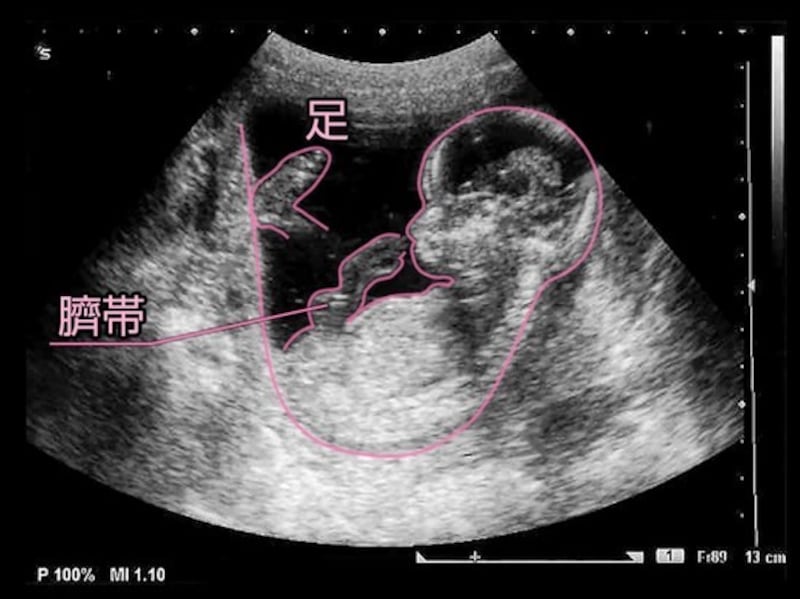

妊娠14週目の胎児の発達

- 妊娠14週目:受精から84~90日目

- 胎児の大きさ:頭殿長(CRL)が80~93mm

- 胎児の体重:25gほど

- 母体の変化:お腹の張りや痛みを感じることも

妊娠14週(14w)になると、胎盤も完成に近づいてきます。胎動はまだわかりませんが、羊水の中を回転するなど赤ちゃんは活発に動くように。

これまではあごと胸がくっついていましたが、首が発達して長くなったため、離れてきます。腕と体の比率は、出生時の様子にかなり近づいてきています。まだ脂肪はついてはいませんが、少しずつ皮膚の厚みが増し、うっすらとうぶ毛が生えてきています。

赤ちゃんの心臓は、もう活発に動いています。心拍数は1分間に150回ほど。お母さんの倍以上の速さで、小さな心臓を目一杯使って1日に25L弱の血液を全身に送り出しています。 健診で心音を聴いてみるとよいでしょう。また、各器官も成熟が進み、脳細胞をつなぐ配線の神経回路もできてきます。